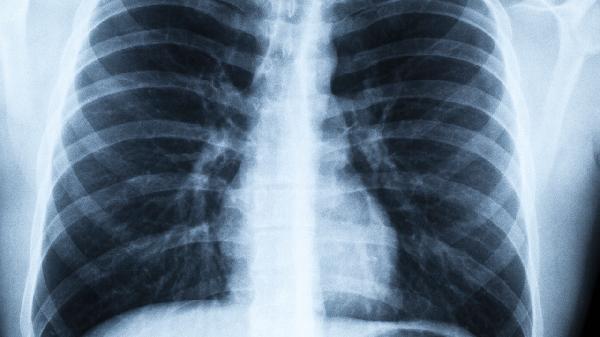

当出现危险信号时,建议48小时内进行肺部听诊和影像学检查。记住,肺炎不是突然发生的,而是被忽视的感冒悄悄演变而来。及时捕捉身体的求.救信号,才能守住呼吸健康的第一道防线。